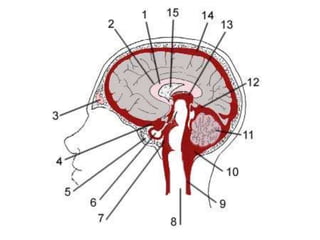

ESPACIO

SUBARACNOIDEO

VCENTRICULOS

LIQUIDO CEFALORRAQUIDEO

CISTERNAS SUBARACNOIDEAS: ENSANCHAMIENTO DEL ESA

ARTERIAS Y VENAS

LOCALIZADO

EN LA BASE

DEL CRANEO

DENTRO DE

CISTERNAS

BASALES

LA MAYORIA DE

ANEURISMAS SE

ORIGINAN EN O

CERCANOS A EL

POLIGONO DE WILLYS